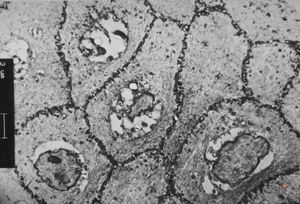

M,66y. | follicular cyst with hyaline Rushton bodies